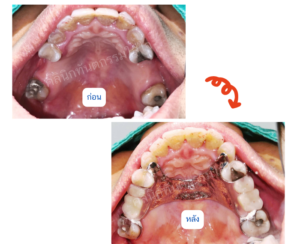

ฟันปลอมชนิดถอดได้

• ฟันปลอมฐานพลาสติก

• ฟันปลอมทั้งปาก

• ฟันปลอมฐานโลหะ